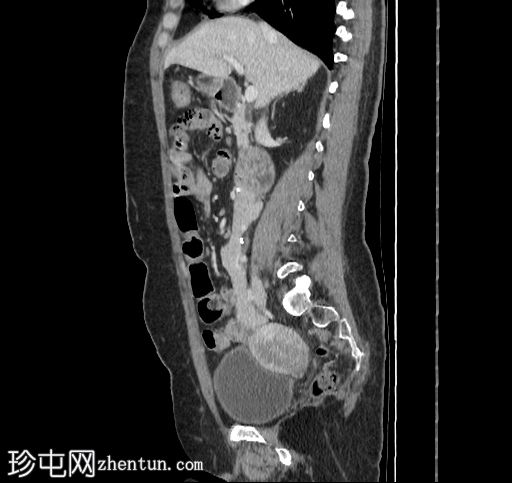

矢状位增强扫描

门静脉期

5.jpg

移植的胰腺位于右侧腹膜后间隙,大小和形态(轴位、冠状位和矢状位)均正常,可见相关手术缝合线。供体十二指肠段与自体十二指肠吻合。可见胰腺移植物与右髂血管的动脉吻合,胰腺实质强化均匀,提示移植物灌注良好。

本例中,影像学检查显示原位肾脏和胰腺明显萎缩,符合长期糖尿病合并慢性肾脏病的表现。肾移植位于左髂窝,与同侧髂血管的动脉和静脉吻合通畅,肾实质均匀强化,这些影像学表现均符合功能性肾移植的影像学特征。移植胰腺位于右侧腹膜后,形态和位置均符合原位胰腺,供体十二指肠袢与原位十二指肠吻合良好。